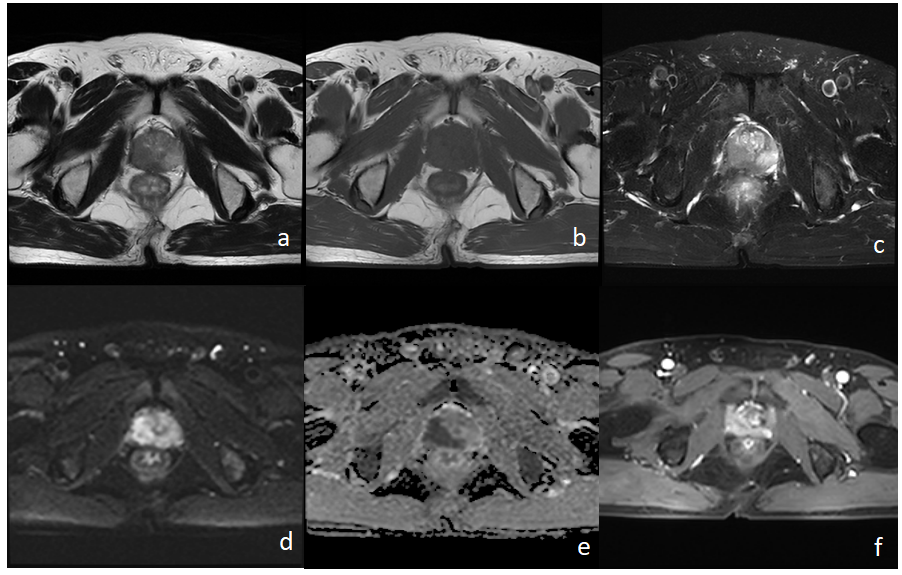

患者男72岁 反复肛门部坠胀、便不尽感3+月。

4月6-7日 前列腺MRI

a-c:前列腺右侧份(以外周带为主)T1WI斑片状等低信号影,T2WI低信号影

d-e:病灶DWI上呈高信号,ADC上呈低信号(弥散受限)

f:增强扫描病灶明显强化

1. 患者肿瘤标志物(PSA↑)异常,提示前列腺有问题,建议做MRI。

2. 常规MRI示前列腺右侧份斑片灶,DWI示病灶弥散受限,增强扫描病灶明显强化,提示前列腺Ca可能(需与慢性前列腺炎鉴别).